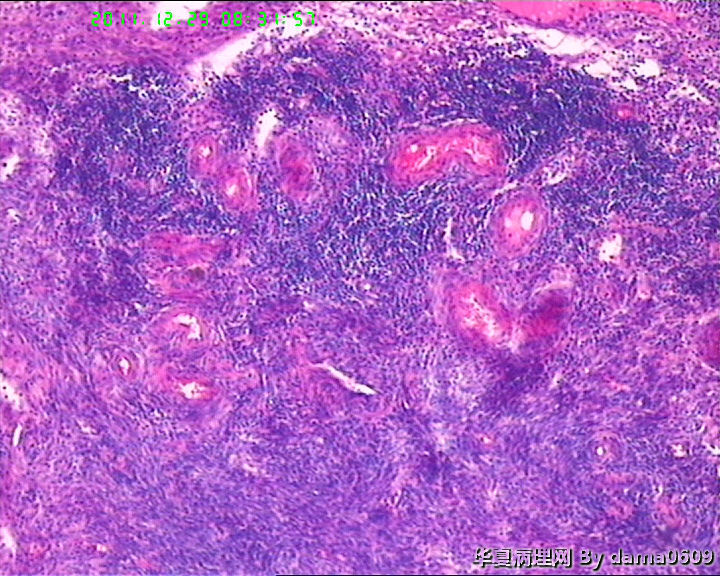

另一为小块囊壁样组织。镜下见卵巢间质内大量淋巴细胞、嗜酸性粒细胞浸润,间质出血。囊壁囊腔一侧见组织细胞、嗜中性粒细胞浸润,小血管增生(图1-9)。局灶见较多的平滑肌组织,内见有异位的子宫内膜组织(图10、11、12)。另于平滑肌组织间见到散在的小腺体(图13~30)。学生不解:1、老年人卵巢内可以出现平滑肌组织,如卵巢门处。此例如此多的平滑肌是正常的吗?   2、平滑肌间的小腺体若是异位的子宫内膜腺体但周围不见内膜间质成分。若非内膜异位腺体,学生又不知如何解释,尤其图19、20、21。请老师们指点迷津。感谢!!

• 感谢老师们一年来的支持,年终岁尾最后一贴,请老师们指教!!图1

图1